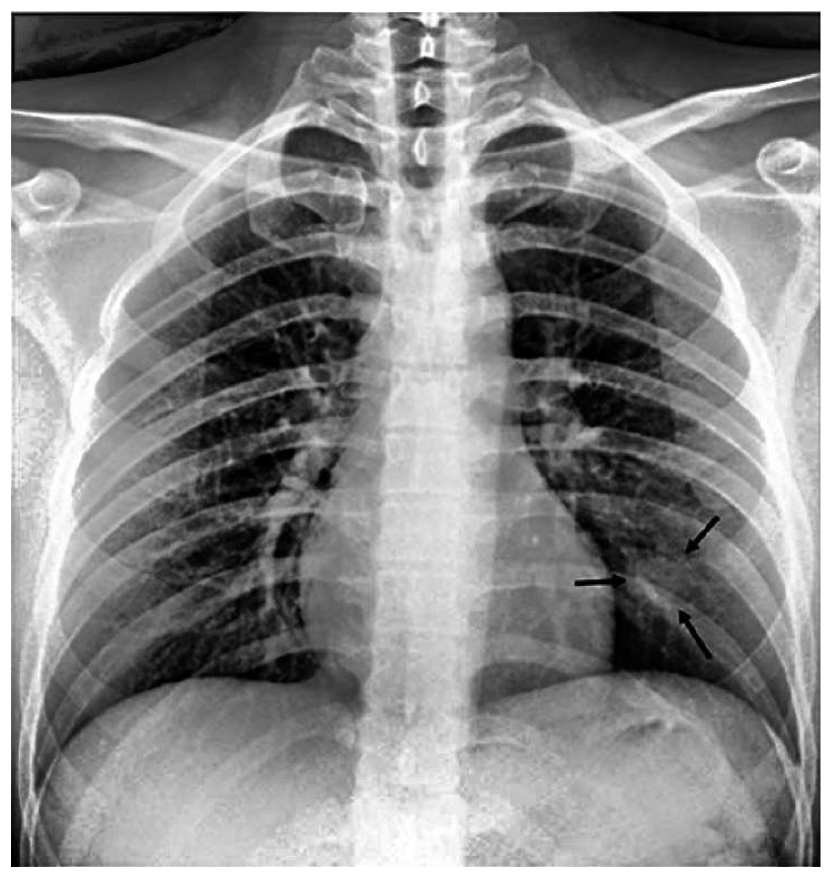

The most common imaging technique used as the first clinical step for chest-related diseases is CXR [26]. Hence, more CXRs could be collected publicly than CT images. A batch of randomly selected samples from the dataset with frontal view, also known as anteroposterior (AP) or posteroanterior (PA), is shown in Fig. 1.

Figure 1: Randomly selected frontal CXR images from different sources